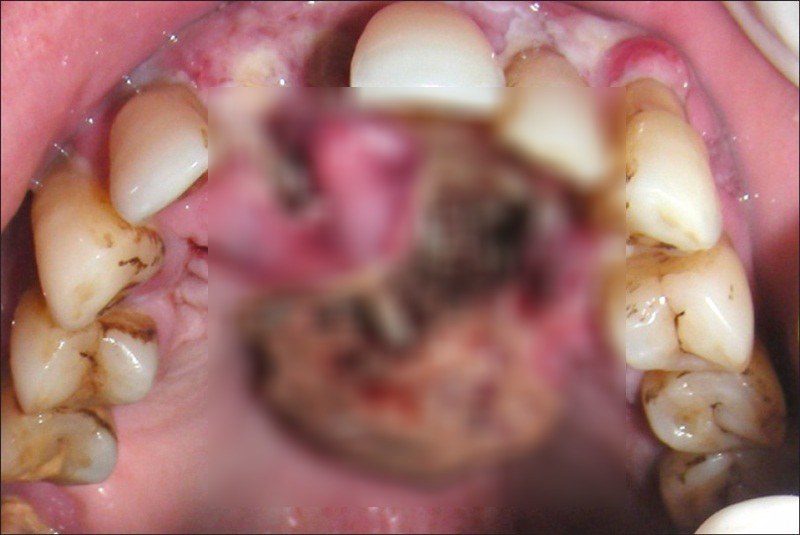

7. Noma โรคมะเร็งช่องปากซึ่งหลังจากเกิ